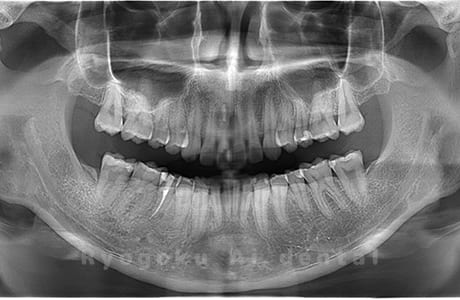

Case01

-

- 原因

- 水平埋伏智歯

- 治療内容

- 下顎の水平埋伏智歯を抜歯

<リスク・副作用>

手術後は痛み、腫れ、痺れなどの副作用が生じる場合があります。